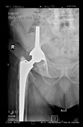

The direction of the cup stem was determined by the guide wire. The aiming device was needed to introduce this wire. After removing the aiming device, the next step was the drilling. Since a cannulated drill bit was used, the previously installed wire could guide the process. A self-positioning reaming tool was then used in the drilled channel. In the prepared cavity, the cup was fitted perfectly. Of the two stemmed cups available to us, the McMinn cup (Waldemar Link, Hamburg, Germany) had the simpler geometry and was therefore chosen. The stemmed cup was inserted according to the manufacturer’s recommendation. In the presence of a significant bone defect, a synthetic bone graft may be impacted for substitution.

The radiological examination allowed us to verify the close bone-to-implant contact and the unchanged position of the implant during follow-up.

In all the cases operated with the above-described targeting procedure, the stems of the cups remained between the cortical bone surfaces without perforation of the linea terminalis, as shown by postoperative radiographs. There were no complicated surgical situations. In 16 cases, the wound healings were uneventful, and the hips were able to bear weight again after postoperative rehabilitation.